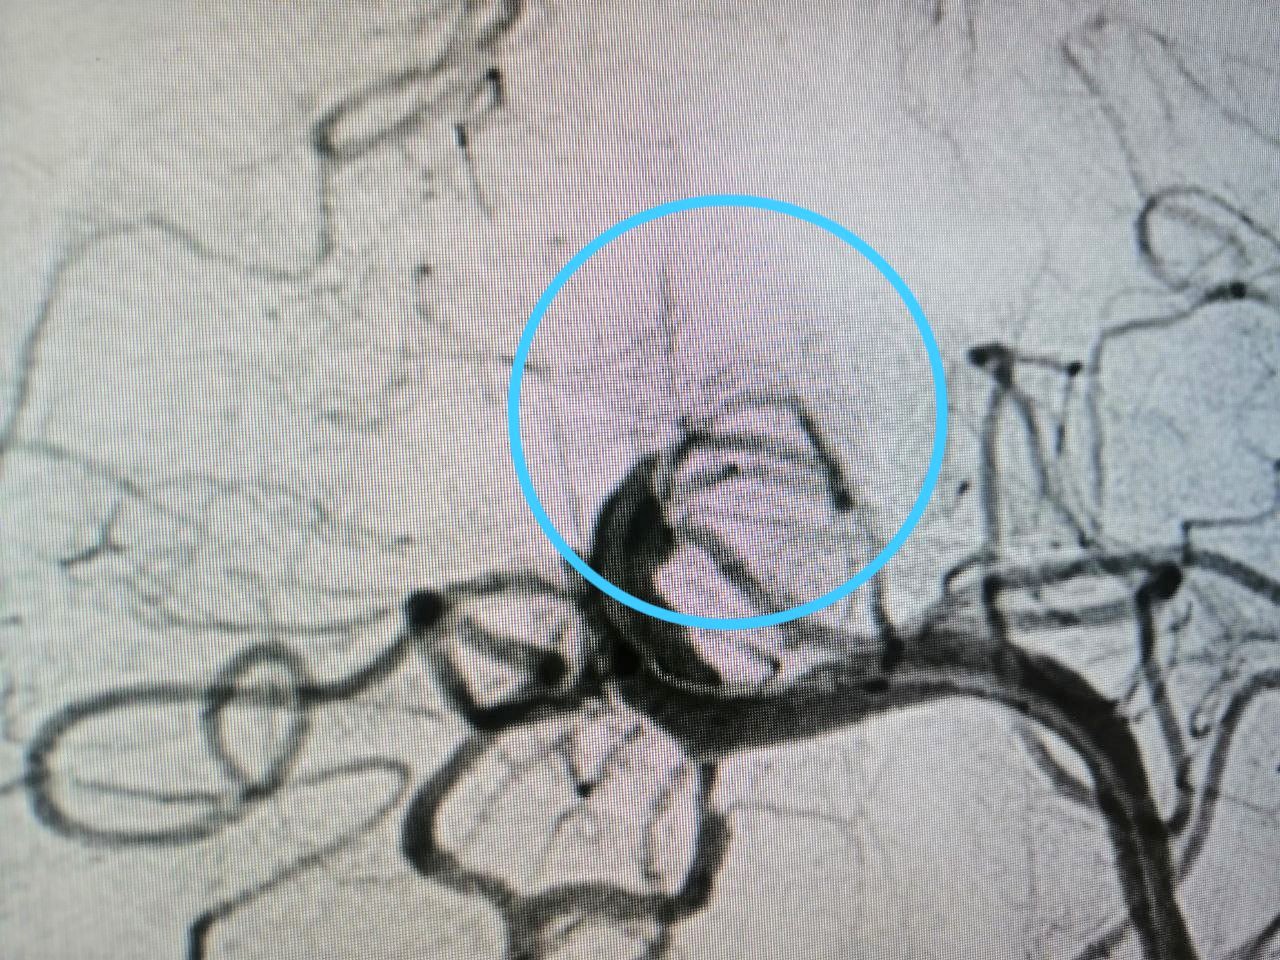

Обследование показало, что у пациента закупорен один из главных сосудов головного мозга – базилярная артерия. На фото №1 хорошо видно место, где резко обрывается кровоток. При тромбозе базилярной артерии летальность достигает 95%, а больше половины выживших обречены на глубокую инвалидность, вплоть до вегетативного состояния. Только при оказании своевременной и грамотной специализированной медицинской помощи появляются шансы на спасение. Пациента подняли в рентген-операционную, где заведующему отделением рентгенохирургических методов диагностики и лечения Максиму Бессмертных вместо планируемой одной операции пришлось в экстренном порядке выполнить сразу три.